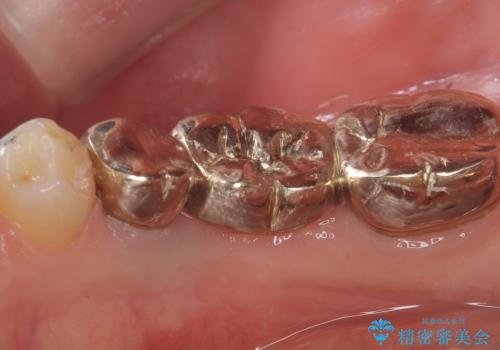

- 主訴:つい先日入れたセラミック(ジルコニア)ブリッジが奥歯部分で割れた。いつも同じ場所で壊れる。これで3度目。

セラミックに比べ、割れづらい金属(ゴールドでのブリッジのやり替えとなりました。

セラミックに比べ、破折リスクの少ない金属を使用したブリッジでのやり替えとなりました。

両支台歯が失活歯のため、どちらかもしくは両方の歯が破折した際、再度ブリッジを除去した治療が必要になるリスクとインプラント治療のご提案もさせていただきましたが、ブリッジでの治療を希望されました。

右下5番は支台歯CR築造を行っています。